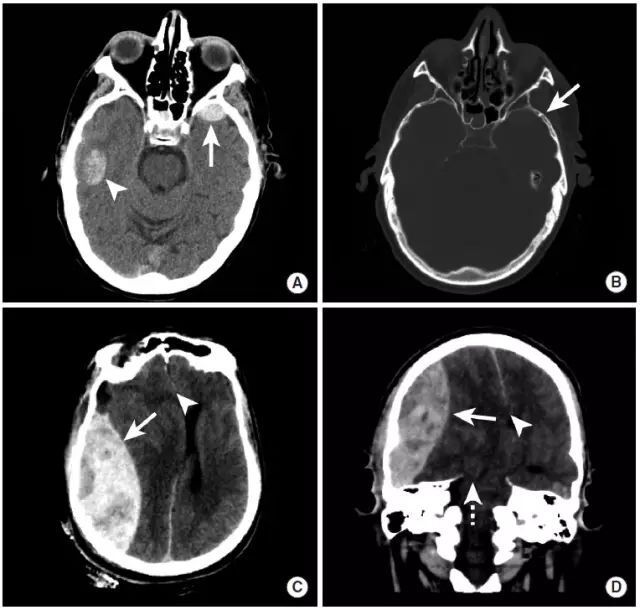

这例双侧颞叶出血伴蛛网膜下腔出血,病因出乎意料

图片尺寸734x694